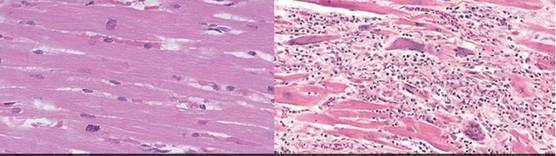

이상 증세는 현미경을 통한 조직검사에서 드러났다. 떼어낸 35개 심장 검체 중 9개에서 심근염 징후가 발견됐다. A씨는 사망 17개월 전 혈압이 상승(156/94mmHg)한 병원 기록을 제외하면 다른 특이점이 없었다. 조직 검사 결과는 세 가지로 요약된다.

첫째, 심방벽에서 심근염이 확인되었고 염증 주위에서 백혈구 중 하나인 호중구(neutrophil)가 많이 관찰됐다.

둘째, 염증이 없는데도 심근 개별 세포가 떨어져 죽는 현상(단세포 괴사)이 나타났다.

셋째, 좌심실을 중심으로 광범위한 수축띠괴사(심근세포 내 수축띠를 보이는 괴사) 현상이 발견됐다.